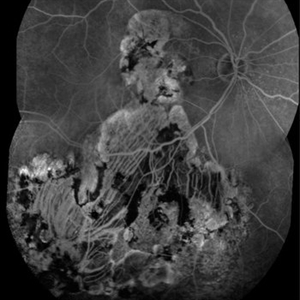

Lady in a dress

Fluorescein Angiography on a 67-year-old male with significant RPE changes secondary to a severe subretinal hemorrhage that required a vitrectomy with subretinal TPA in 2013.

Photographer: Shelby Helton

Imaging device: Heidelberg Spectralis

Condition/keywords: wet age-related macular degeneration (wet AMD)